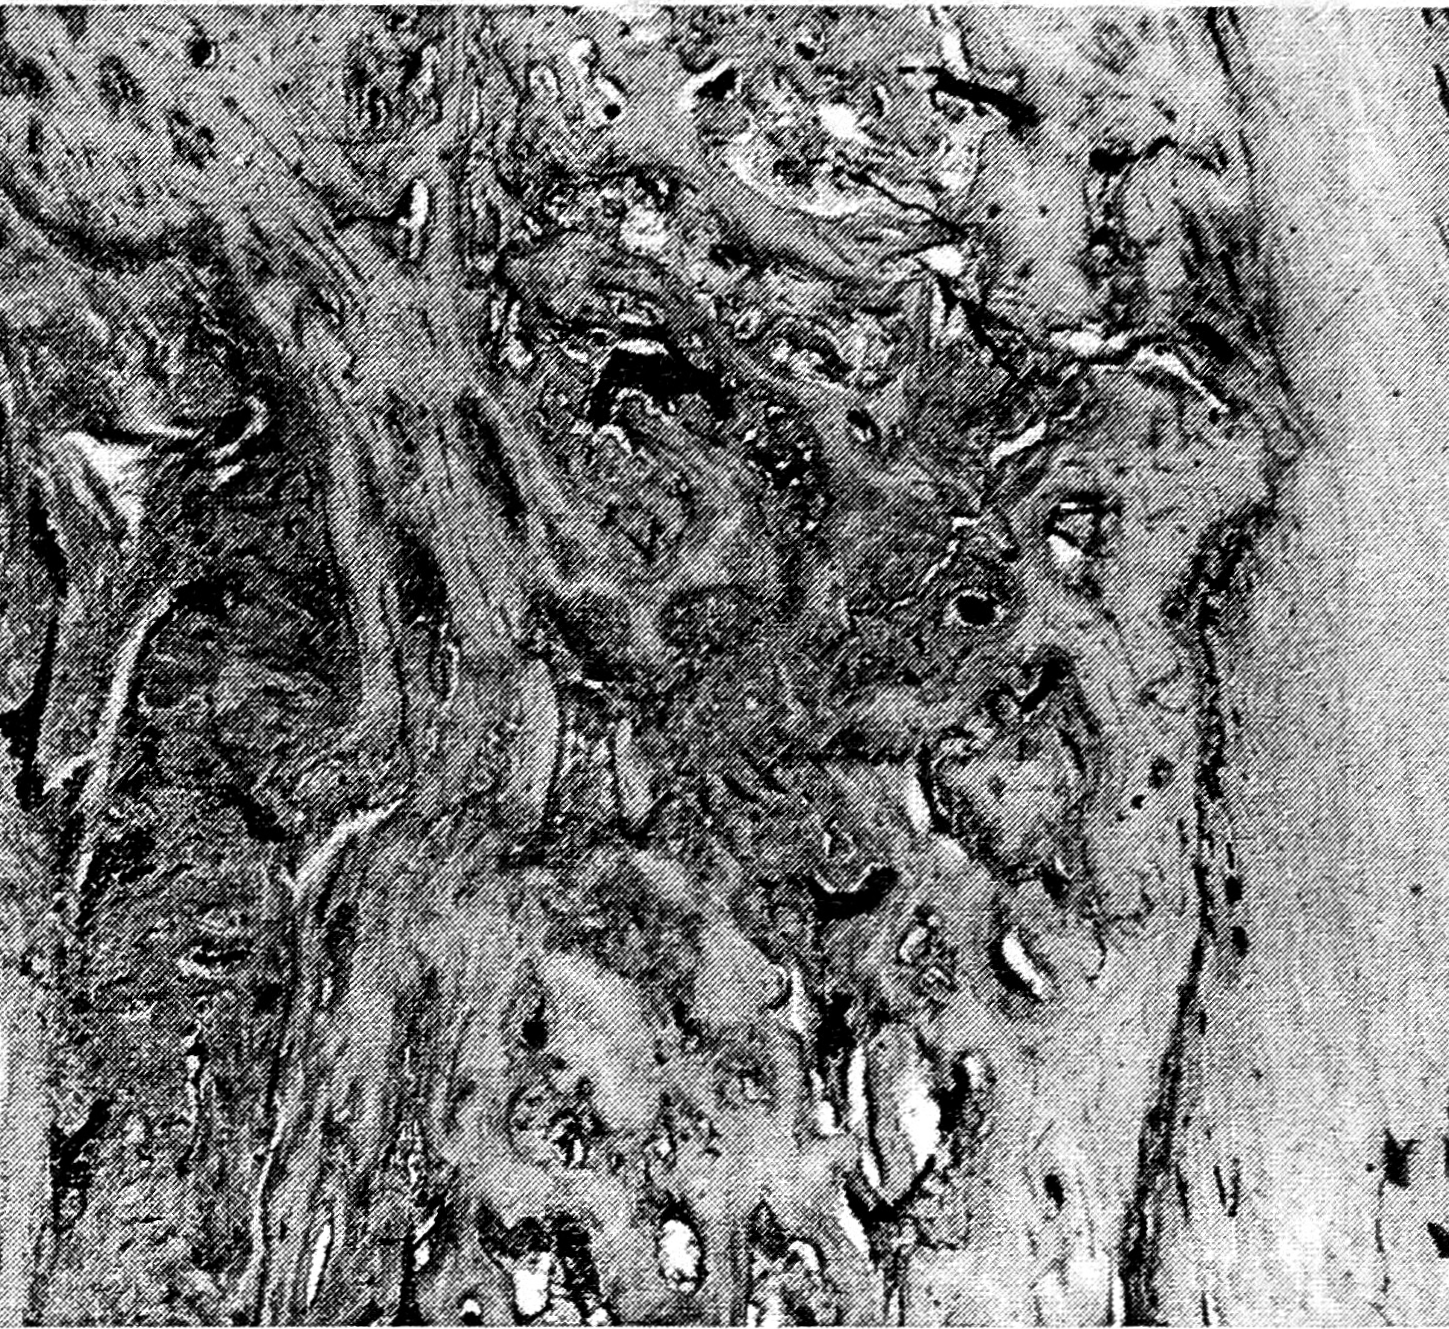

Рис. 4. Распространение щели по поперечнику кости при ползучем переломе: заполнение периферических отделов щели остеогенной тканью (9-е сутки со дня возникновения ползучего перелома).

Гистотопографический препарат. Окраска гематоксилином и эозином. Ув. 60.